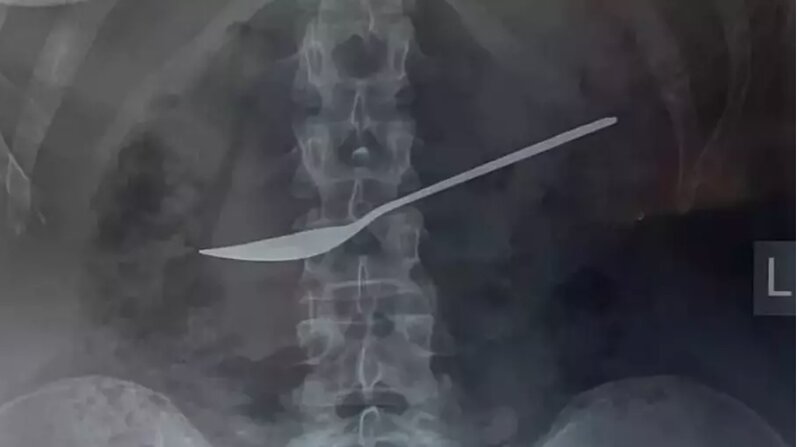

Qarın ağrısı şikayəti ilə həkimə müraciət edən qadının mədəsindən qaşıq çıxarılıb

Qarın ağrısı şikayəti ilə həkimə müraciət edən qadının mədəsindən qaşıq çıxarılıbRusiyanın Voloqda vilayətində qarın ağrısı şikayəti ilə xəstəxanaya müraciət edən qadının mədəsindən 20 sm-lik metal qaşıq çıxarılıb.

Sonxeber.az xarici mediaya istinadən xəbər verir ki, başlanğıcda adi bir ağrı sanılan hadisə rentgen çəkilişi nəticəsində hamını şoka salıb. Dr. Dmitri Vankov özofaqoqastroduodenoskopiya üsulundan istifadə edərək qaşığı təhlükəsiz şəkildə çıxara bilib.

Səhhəti yaxşı olan xəstənin vəziyyəti tibb aləmində rezonans doğurub və erkən diaqnozun vacibliyini xatırladıb.

Bu hadisənin necə baş verdiyi xəstənin tamamilə sağaldıqdan sonra açıqlanacağı gözlənilir.